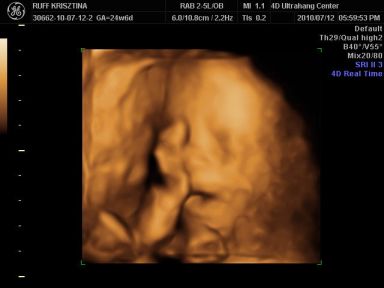

Kri: Brig nagyon cukorfalat a képeken, láccik jol érezte magát. Neked is medence fekvésű volt legutobb? Azt állitolag lehet a mozgásán is lehet érezni hogy merre van. Aztán kitudja...

Cherryke: nagyon édes a kis krapek !!

És neki é tök jol kivehető mindene, de olyan megtévesztő ilyenkor hogy kire hasonlit